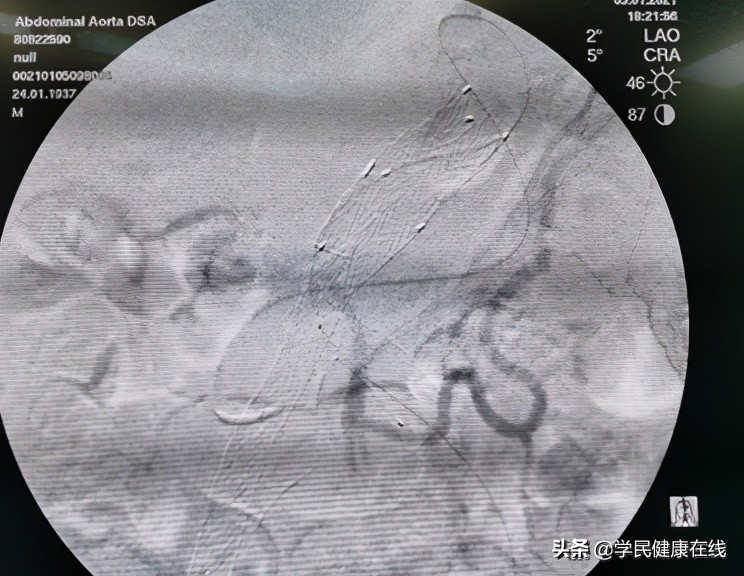

图3.经过漫长的通路到达肠系膜下动脉起始部进行栓塞

对II型内漏的处理目前国内都是采用腔内的方式,比如,经过肠系膜上动脉-结肠中动脉-边缘弓-Riolan氏弓-左结肠动脉-肠系膜下动脉,这条路非常迂曲,漫长,到达肠系膜下动脉起始部就可以填塞弹簧圈。去年底,曾经有个病例,由于器材长度不够,而眼睁睁看着,处理不了。